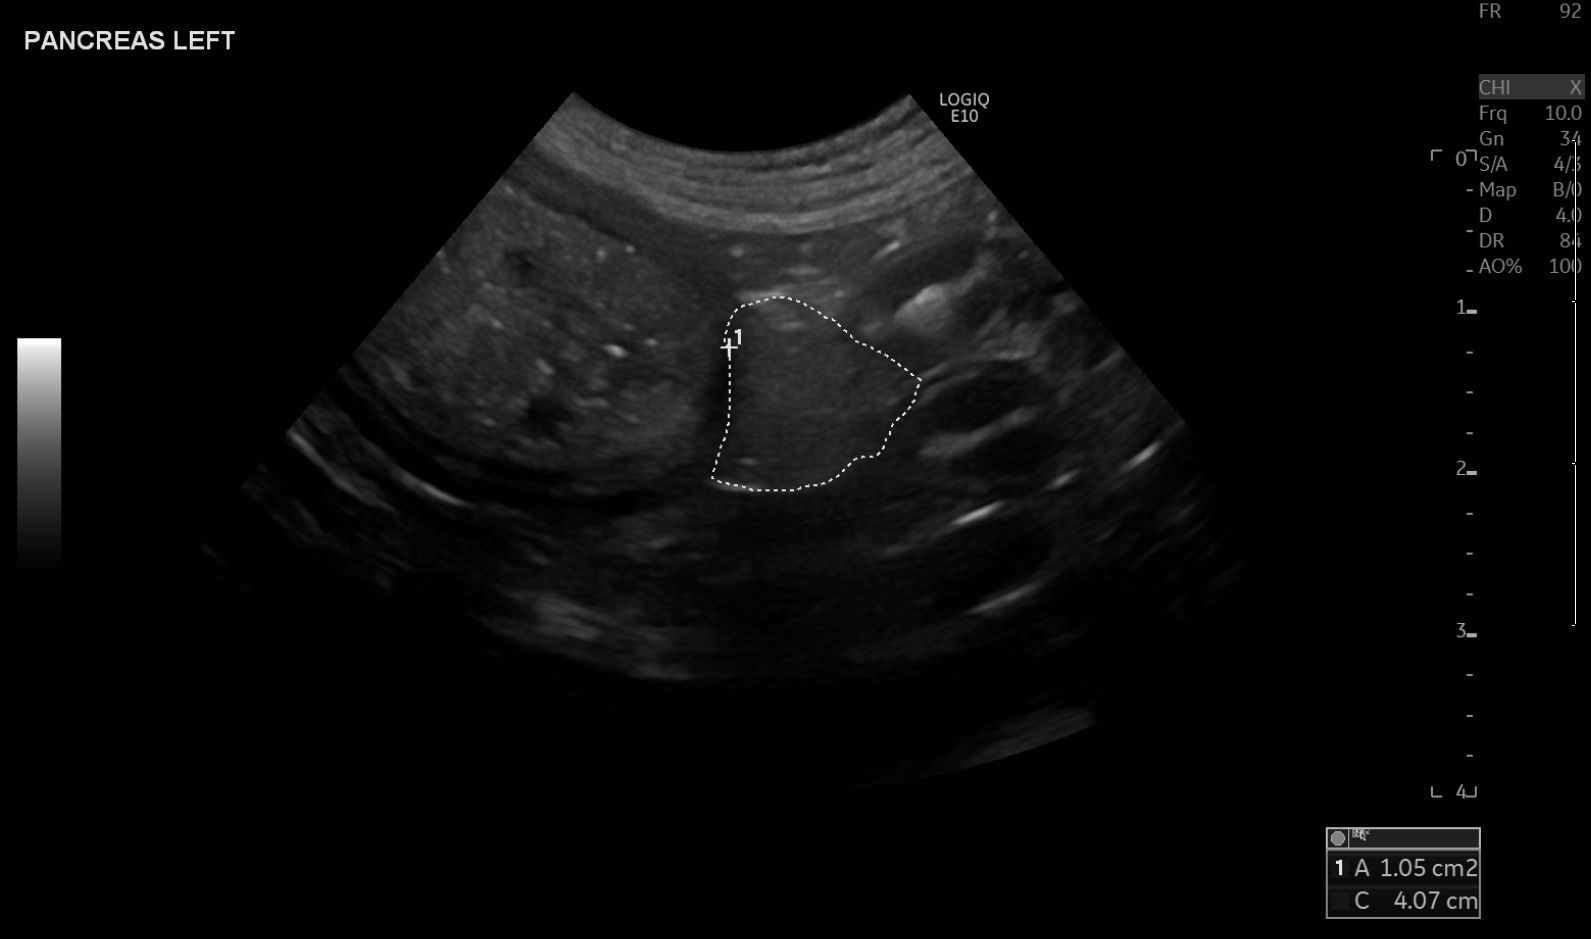

Abdominale Sonografie bei Hund und Katze - Modul 4: Ultraschalluntersuchung von Leber, Gallenblase und Pankreas

Die hepatobiliäre Untersuchung und die Sonografie des Pankreas umfassen die Darstellung der Längs- und Querebenen aller Organbereiche.

Autorin: Dr. Verena Hocke

Bildgebende Diagnostik von endokrinen Organen in der Kleintierpraxis – Teil 2: Hypophyse, Nebennieren und Pankreas

Dieser zweite Artikel zur bildgebenden Diagnostik endokriner Organe in der Kleintierpraxis bietet grundlegende Einblicke in die Bildgebung der Hypophyse, Nebennieren und Pankreas. Es werden praxisnah die Möglichkeiten und Grenzen der verschiedenen bildgebenden Modalitäten beleuchtet und Empfehlungen für die Anwendung im klinischen Alltag dargestellt.

Autorin: Dr. Ursula Teubenbacher (Mag., Dr. med. vet., Resident ECVDI an dem Universitären Tierspital Zürich)